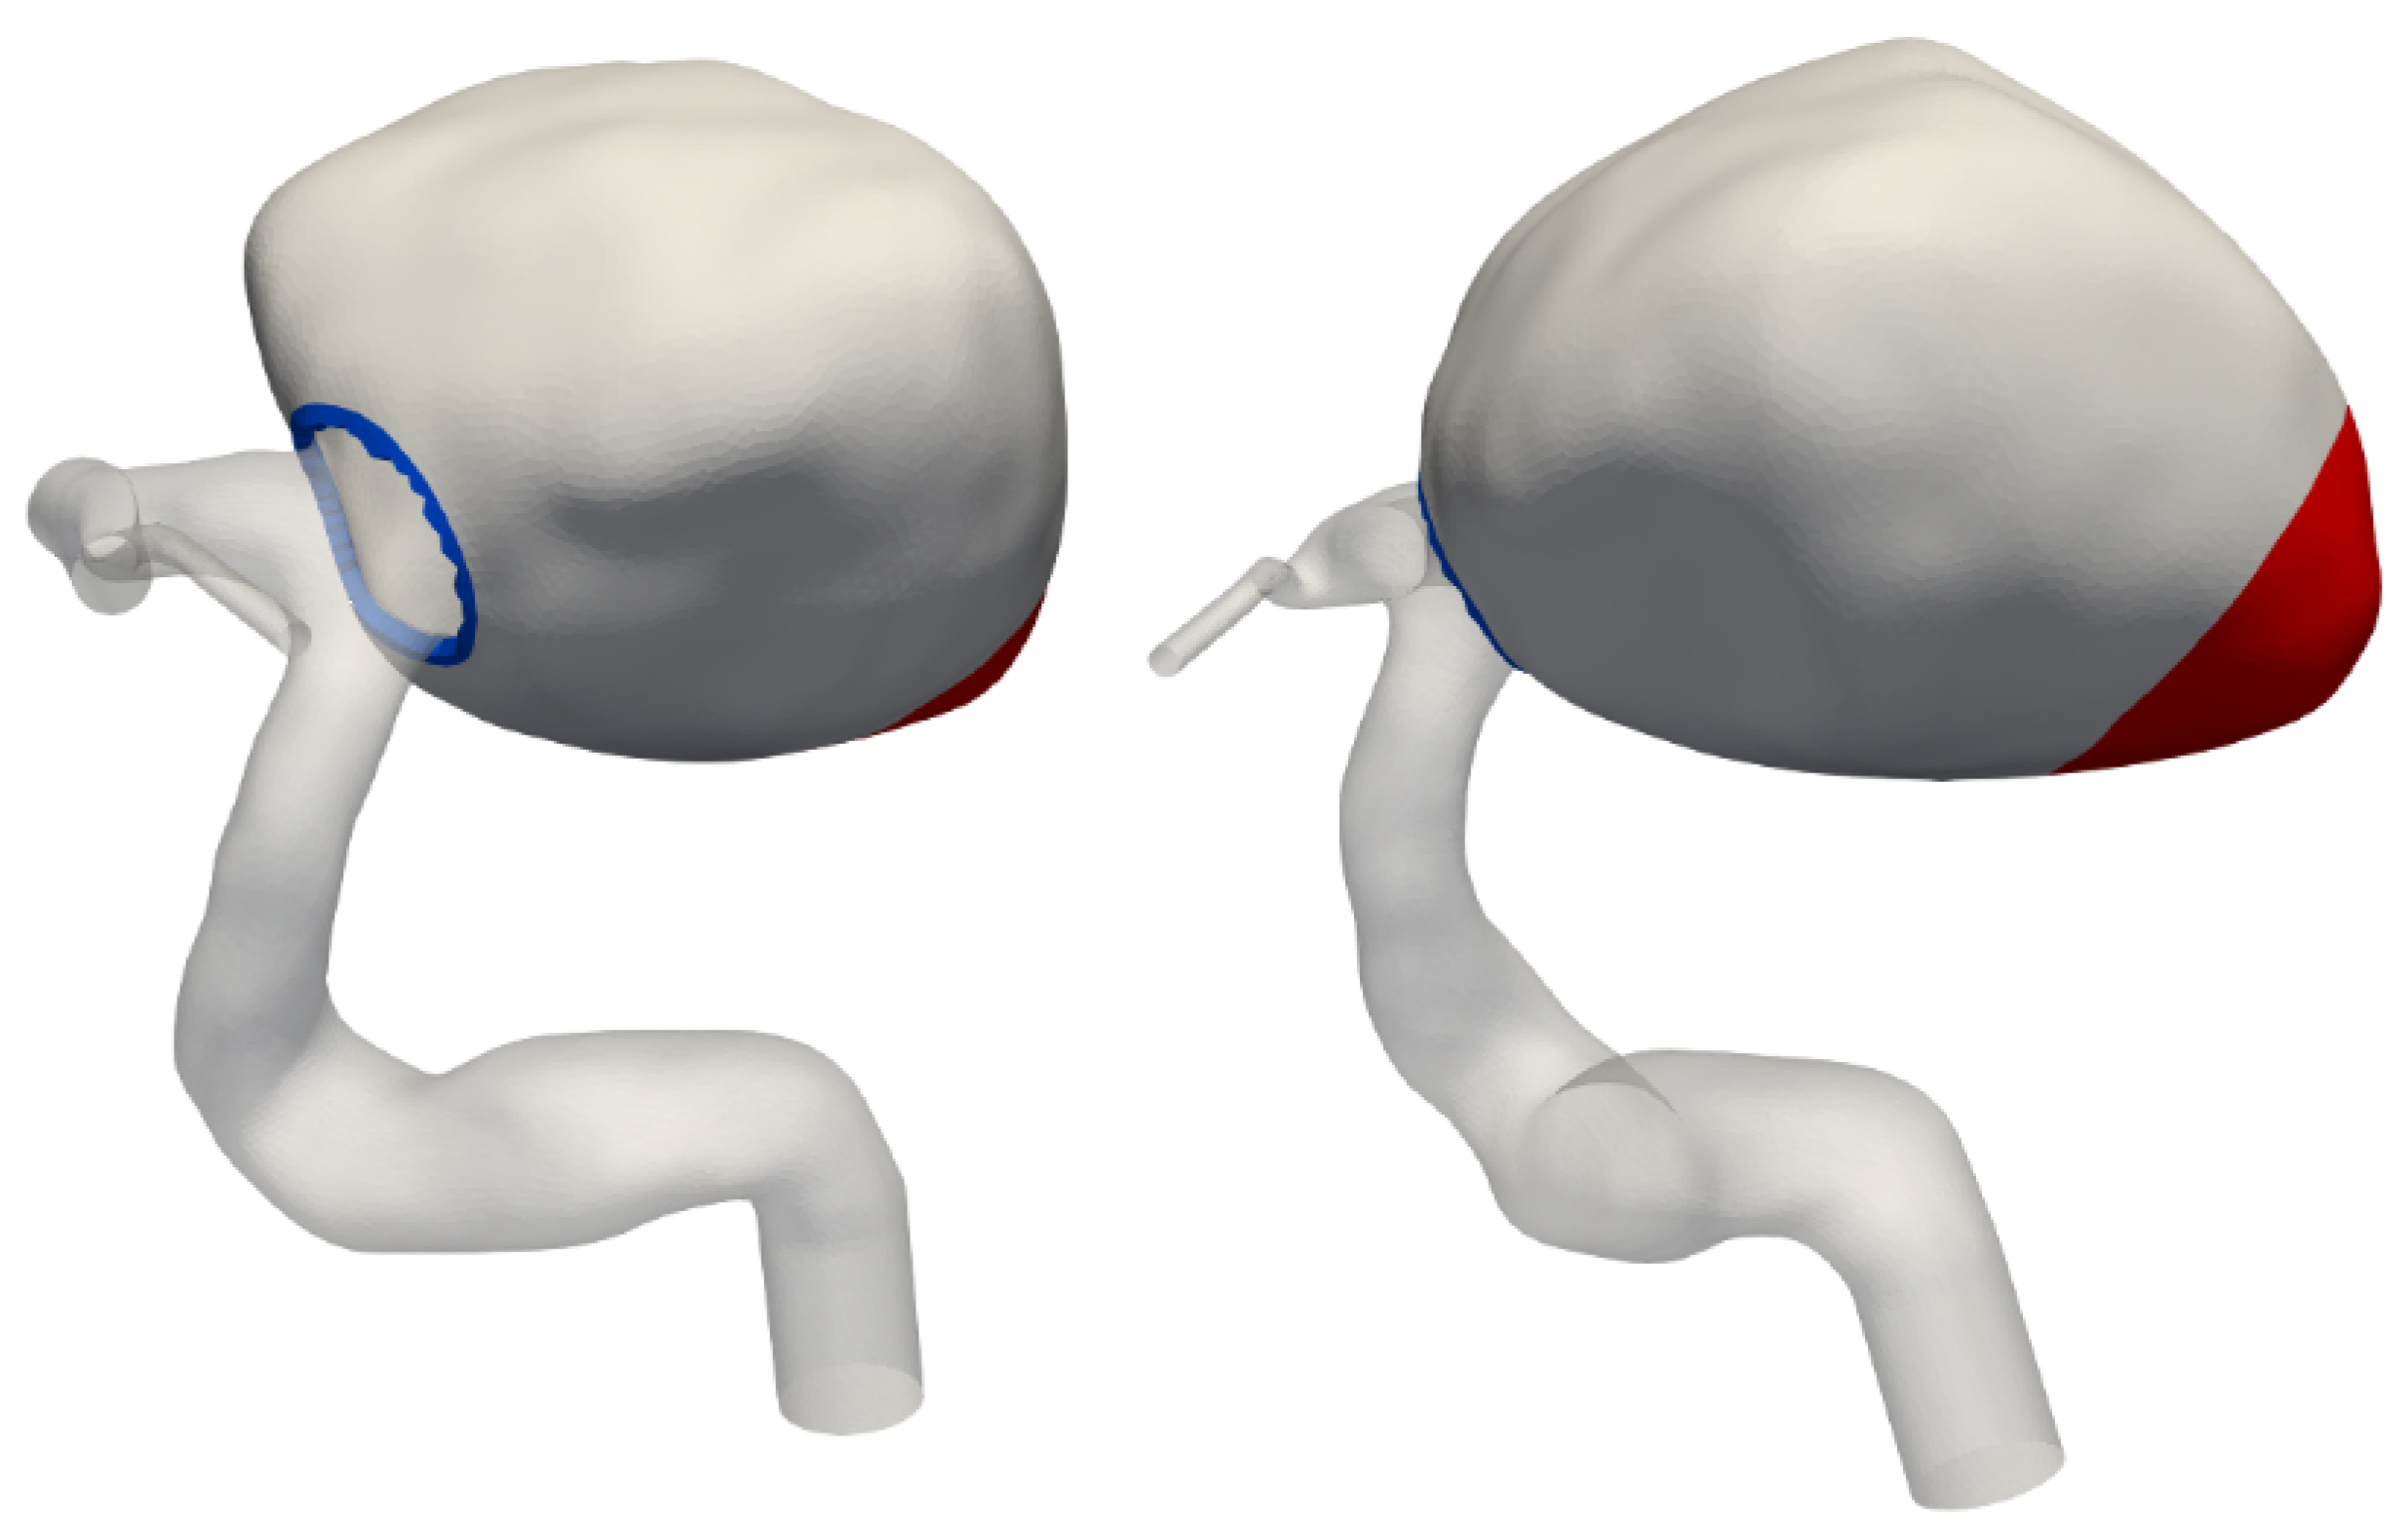

2.2. Mesh Generation